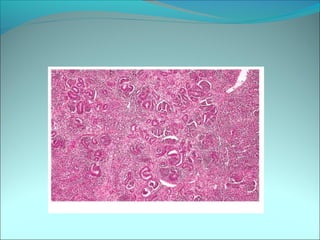

• #44 Diffuse pattern of growth and monotonous cytologic appearance in Ewing sarcoma/PNET

• #45 (A) High-power appearance of uniform round nuclei and indistinct cytoplasmic borders. (B) High-power view of “large-cell” tumor. The nuclei are more pleomorphic than in classic Ewing tumor